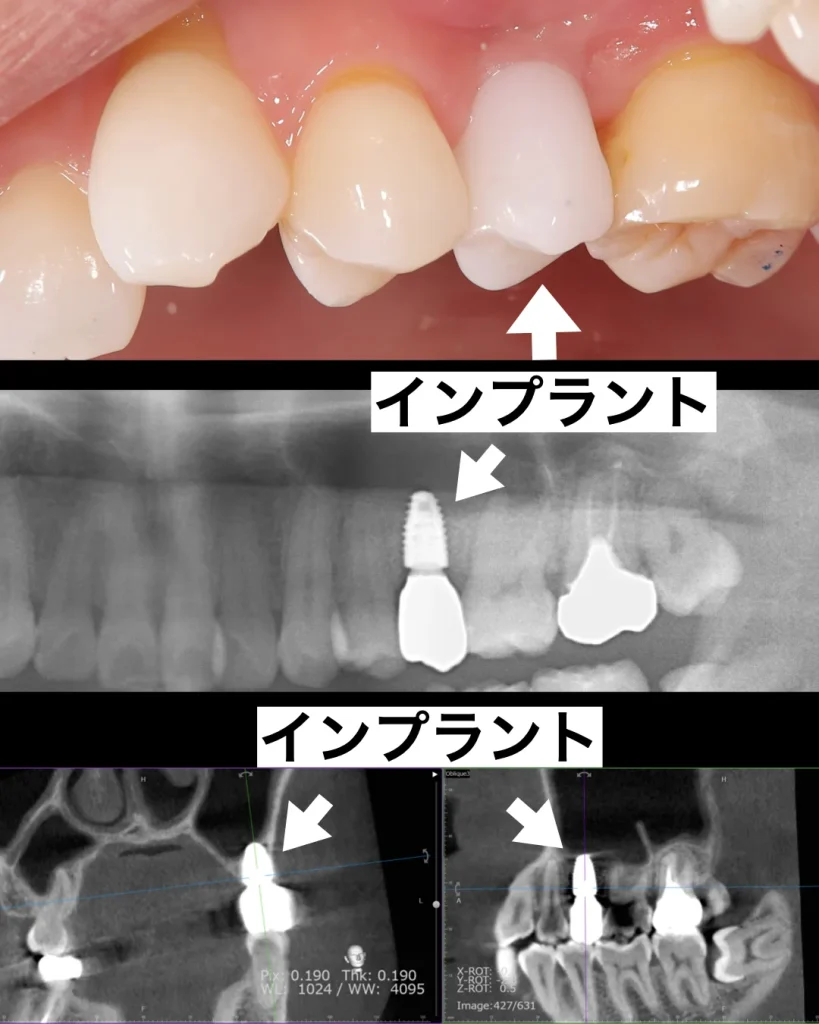

診査・診断の結果、歯の根の中まで虫歯が広がっており、保存は困難で抜歯が必要と判断しました。治療方法としては、インプラントとブリッジの2つの選択肢をご説明し、それぞれのメリット・デメリットをお伝えした上で、患者様はインプラント治療を選択されました。

インプラント埋入

インプラント手術は抜いてその日にインプラントを埋入する抜歯即時インプラントを行いました。この手術のメリットは、抜歯する手術とインプラントを入れる手術を同時に行うことができ、痛みが少なく出血も少なくて済む点です。当院ではこの方法を第一選択として採用し、患者様の治癒期間と痛みを最小限にするようにしています。さらに、今回はソケットリフトと呼ばれるインプラントの先の上顎洞粘膜を押し上げる手術も同時に行いました。

1ヶ月後にISQ値とPT値と呼ばれる、インプラントと骨との結合度合いを測定する機械で確認した後、問題なくしっかりとした値が出たので、仮歯を装着しました。